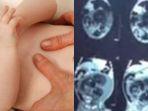

Kondisi Asli Bayi Laki-laki Hamil di Sumbar, Berobat ke Dukun hingga Besok Operasi, Dokter: Tumor

Kondisi asli bayi laki-laki hamil di Sumbar yang viral di media sosial. Dokter yakini idap penyakit serius. Akhirnya besok akan dioperasi.